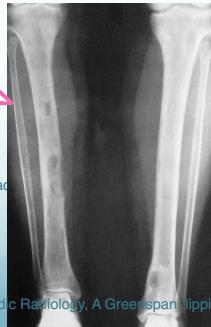

- Sub-periosteal resorption: middle phalanges, tibial shaft

DEXA: Dual Emission X-ray Absorptiometry Demineralization of long bones, Pathological fracture

- In hand, sub-periosteal bone resorption .This change usually happen in the middle phalanges, radial aspect in the 2nd or 3rd finger.

Sub-periosteal bone resorption

- Most useful sign

- Virtually Diagnostic

- Location

Subperiosteal bone resorption (straight arrow), resorption of the tip of the terminal phalanx and the altered bone architecture. Arterial calcification is also present (curved arrow).